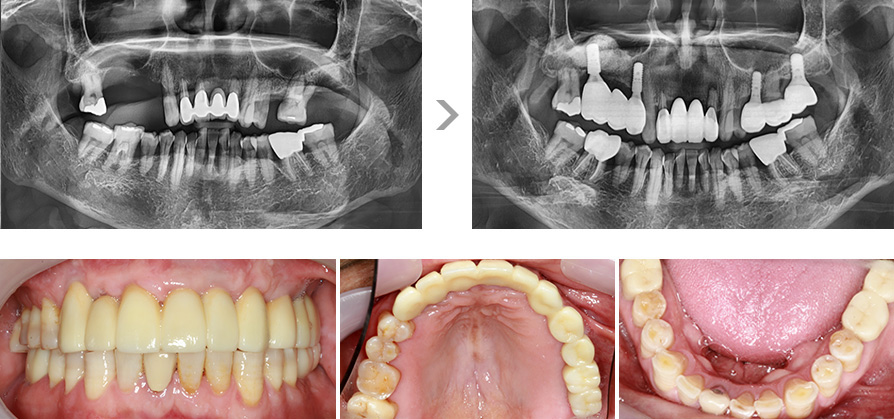

상악 치아 상당수와 하악 치아 대부분이 손실되어 전체 임플란트를 진행하였습니다.

치아 상실 후 오랜 시간이 지나 상악동 거상술을 통해 임플란트 식립이 가능한 잇몸뼈 높이를 만든 후 임플란트를 식립하셨습니다.

위 턱뼈에는 코와 뺨 사이의 빈 공간인 상악동이 존재합니다. 이 상악동 공간에 임플란트를 심을 수 있는

충분한 양의 뼈를 확보하지 않을 경우, 식립된 임플란트가 빠져버리거나 입 천장 쪽에 구멍이 나는

부작용이 생길 수 있습니다.